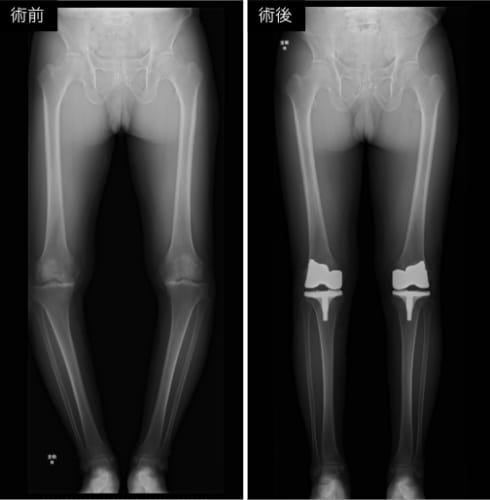

変形性膝関節症に対する人工膝関節置換術

変形性関節症や関節リウマチ、骨壊死などにより関節の疼痛や機能障害が高度となり、保存療法で十分な改善が得られない症例を適応として行っています。障害された関節を人工材料に置換することで、疼痛の軽減、可動域の改善、ならびに日常生活動作の回復が期待されます。股関節や膝関節に加え、肩関節、肘関節、足関節など幅広い関節に対して施行しています。特に股関節および膝関節では、術前計画に基づくインプラント選択と正確な設置が長期成績に重要であるため、ナビゲーションやロボットなどの手術支援技術を活用し、精密かつ個別化された治療を行っています。